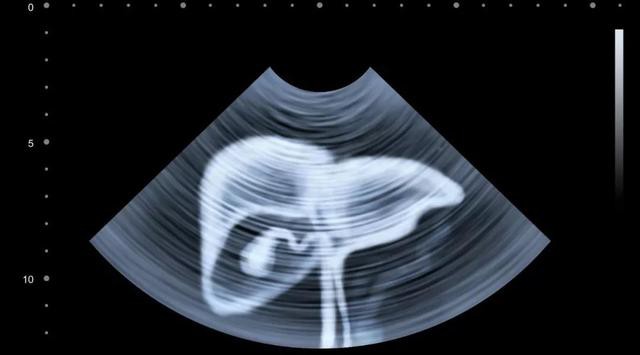

Nếu bạn thuộc 3 nhóm người đầu tiên (viêm gan B, xơ gan, có người nhà là bệnh nhân ung thư gan): Nên xét nghiệm siêu âm B bụng + alpha-fetoprotein huyết thanh (AFP) mỗi 6 tháng;

Nếu bạn thuộc 2 nhóm người sau (hơn 40 tuổi, thích uống rượu): Nên đi khám sức khỏe mỗi năm một lần và nếu phát hiện thấy sự bất thường thì phải kiểm tra sức khỏe chuyên sâu.